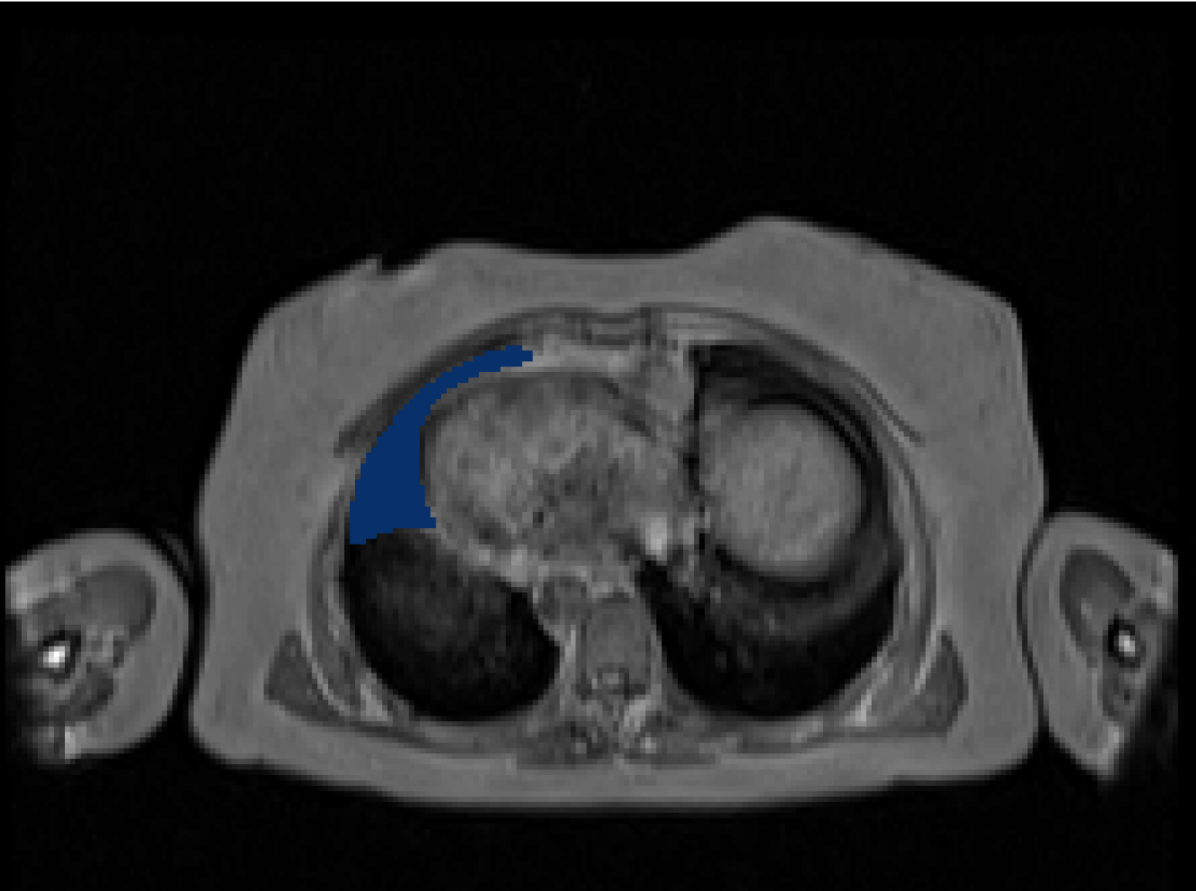

Manual Labels for Verification. We design a mechanism to validate these collected labels by humans. To do so we collect manual labels from 3000 2D image from 300 MRI samples for 10 abdominal organs (UKBOB-manual). These manual labels (see examples in Figure 2) act as a validation for the large UKBOB dataset. On these labels, the UKBOB automatic labels obtain an average Dice Score of 0.891 (see Table 3). Furthermore, we verify the spine labels of UKBOB using previously collected manual labels of 200 3D spine labels [5]. We show an example in Figure 1 and we see how the new collected labels match the manual labels in the spine with a total Dice score of 0.811, indicating accurate labels. We discuss in Section 5.1 another mechanism for verifying the labels by zero-shot generalization of trained models to other similar datasets that has manual labels.